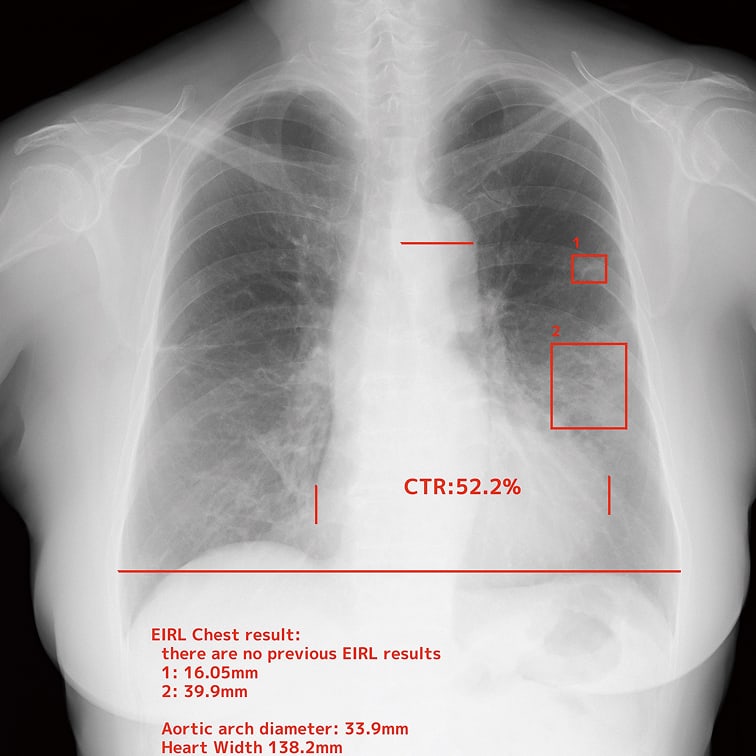

結節影等*の異常陰影を検出

心胸郭比等**の自動計測

※画像はイメージです ※EIRL Chest Screeningは製品の総称です *結節影、浸潤影、無気肺、間質性陰影 **胸腔内の空気含有面積、心胸郭比、縦隔幅、大動脈弓の径、肋骨横隔膜角、経時比較

EIRLが検出した箇所を、明確に矩形で表示します。これにより、原画像の情報を損うことなく、直感的に検出箇所を確認できます。

EIRLが胸部X線画像上のランドマークを認識し、自動で計測。計測のばらつきを抑えながら、日常業務の負担を大幅に軽減します。